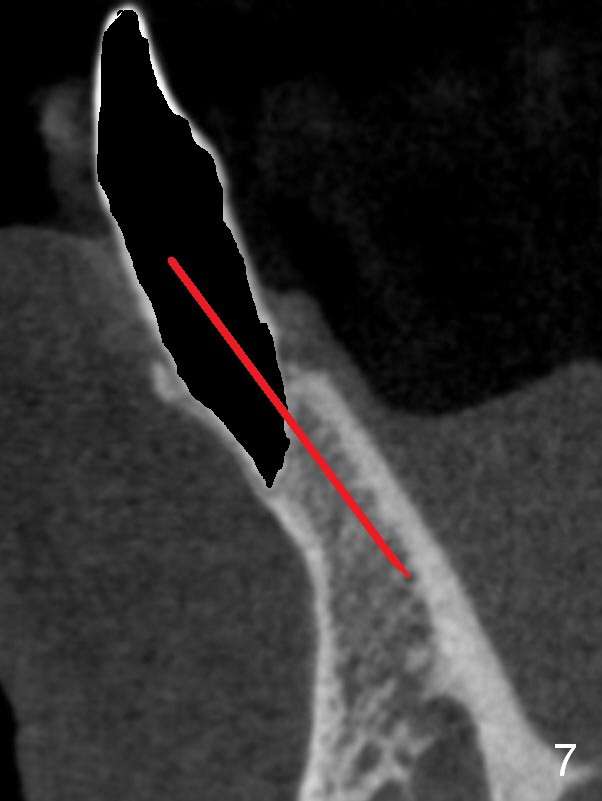

A 74-year-old man has several missing teeth (Fig.1). His 1st goal is to replace the lower left lateral incisor (Fig.2). The residual root has an apical lesion (Fig.3 *). To describe intraop findings, a CT image of a different patient is used (Fig.4 coronal section; B: buccal; L: lingual). After extraction, the buccal plate is found to be thin and low (Fig.5 arrowheads). A 1.5 mm pilot drill (Fig.6 red line) is used to initiate osteotomy in the lingual plate of the socket. Once the drill penetrates the lingual plate, the trajectory changes and the depth is 17 mm from the gingival margin (Fig.7). A PA is taken (Fig.8); it appears that the osteotomy can be extended more apically. When the pilot drill extends to 20 mm, there is sudden empty feeling. The lingual plate has perforated (Fig.9). A new osteotomy is established buccally (Fig.10 pink). To avoid buccal plate perforation, especially in the buccal undercut area (>), the coronal end of the drill has to be tilted buccally (<--). An angled abutment (3x20 mm, 15°) is placed (Fig.11,12). The abutment is modified (Fig.13,14) to accommodate an immediate provisional (Fig.15,16 P). Perio dressing is to be applied to prevent the bone graft from getting dislodged buccally (Fig.15). The dressing is in place 7 days postop (Fig.17).